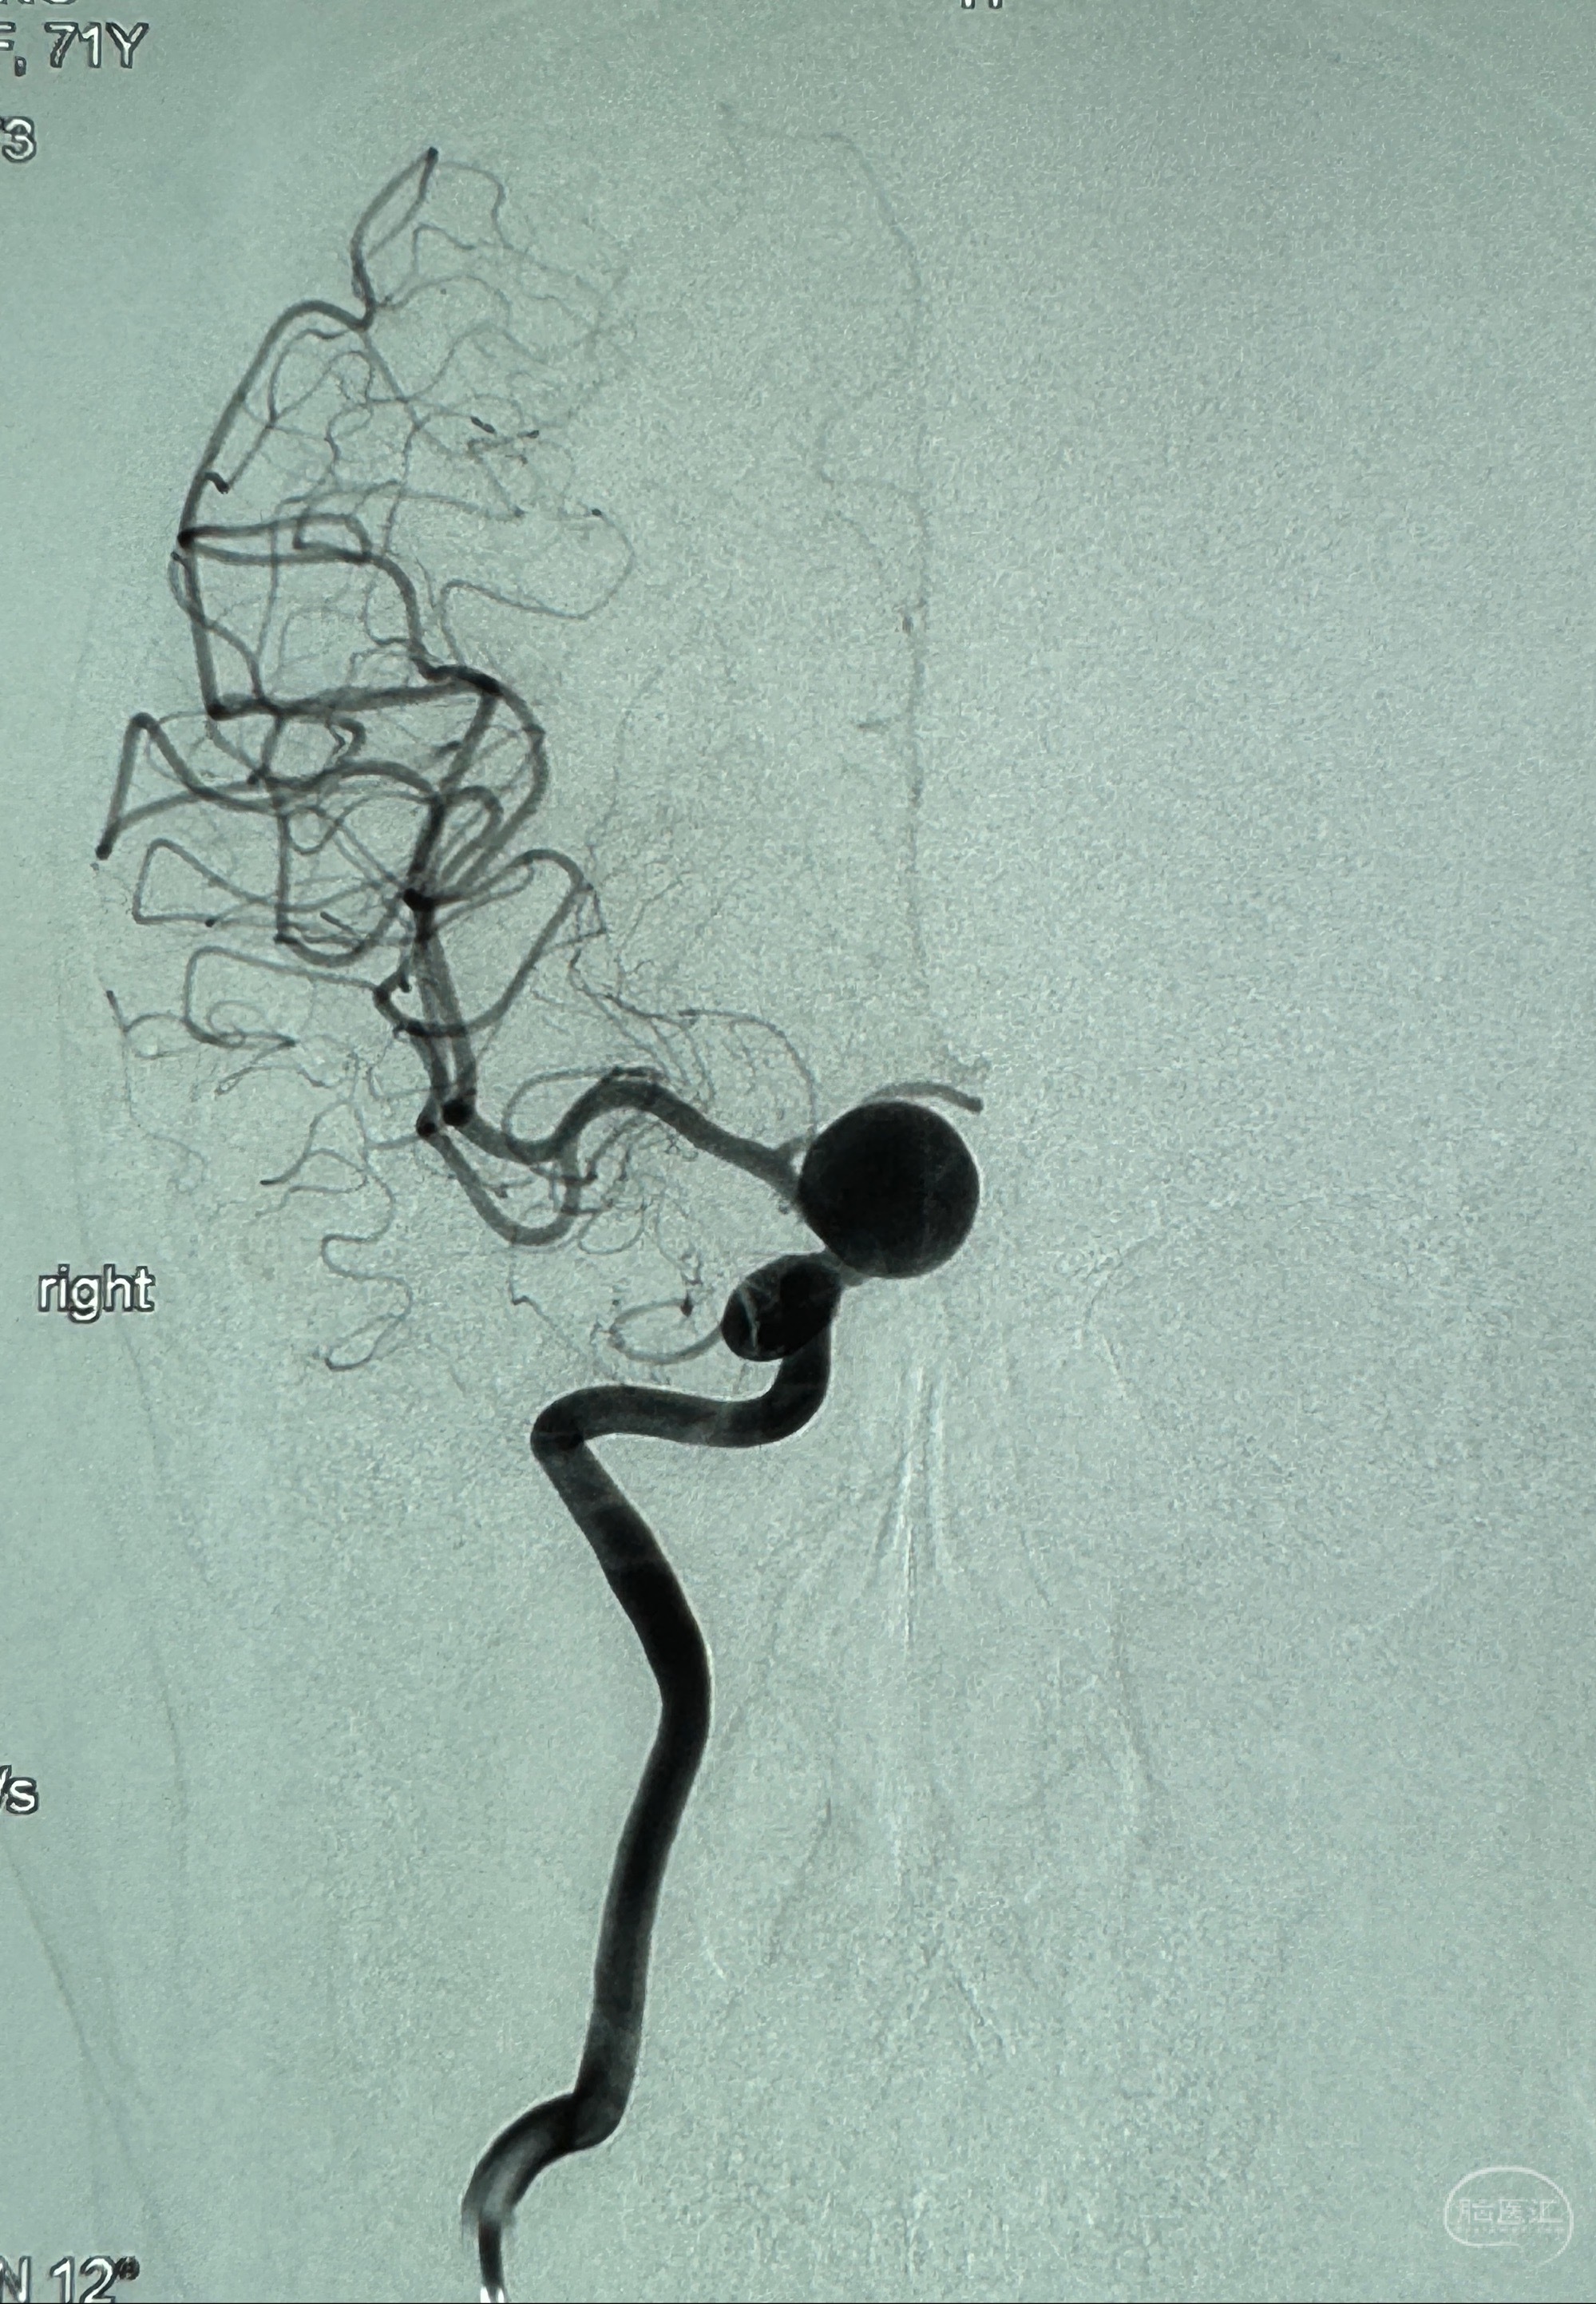

2023-12-08外院DSA:右侧颈眼动脉瘤,约13*12mm大小,压颈试验显示左右向及后向前代偿可

2023-12-18全麻下行DSA➕密网支架植入备弹簧圈辅助栓塞

2023-12-27术后第十天复查DSA

支架贴壁佳,但可见射流,咋办?